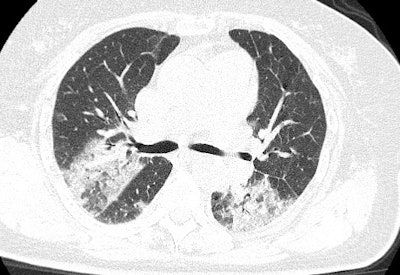

CT scan of a 79-year-old Chinese female with the novel coronavirus who died. Image courtesy of Dr. Yuxin Shi, PhD, from the Shanghai Public Health Clinical Center.In a preliminary effort to address this concern, a group led by Dr. Ali Gholamrezanezhad from the University of Southern California detailed key safety measures for radiology department personnel.